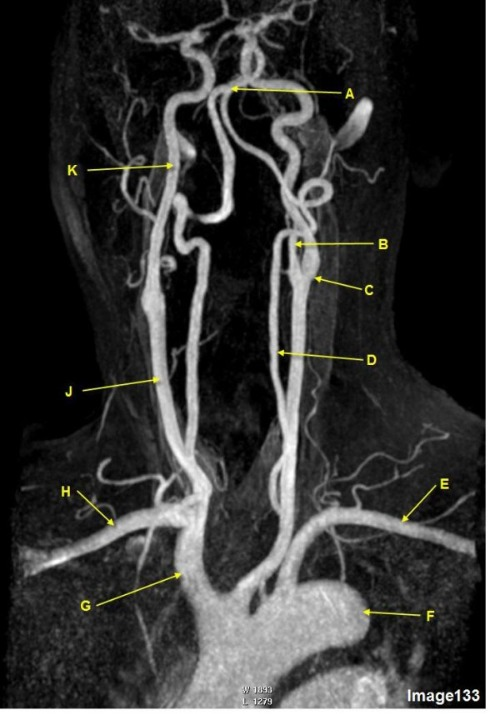

Letter R in Image 137 is pointing to:

A. Pons

Letter N in Image 137 is pointing to:

D. Body of corpus callosum

Letter J in Image 137 is pointing to:

D. Fourth ventricle

Letter H in Image 137 is pointing to:

C. Sulcus

Letter O in Image 137 is pointing to:

E. Splenium of corpus callosum

Letter M in Image 137 is pointing to:

C. Thalamus

Letter X in Image 137 is pointing to:

D. Vein of galen

Letter S in Image 137 is pointing to:

B. Pituitary gland